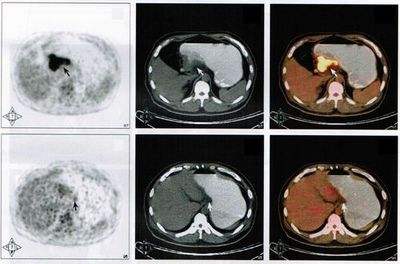

那么什么是PET呢?它的原理又是什么呢?

PET全称为正电子发射计算机断层显像(positron emission tomography PET),是反映病变的基因、分子、代谢及功能状态的显像设备。它是利用正电子核素标记葡萄糖等人体代谢物作为显像剂,通过病灶对显像剂的摄取来反映其代谢变化,从而为临床提供疾病的生物代谢信息。是当今生命科学、医学影像技术发展的新里程碑。

CT全称为电子计算机X射线断层扫描技术(Computed Tomography),它是利用X射线对人体进行体层检查。

PET/CT:将PET和CT有机的结合在一起,使用同一个检查床合用一个图像工作站,PET/CT同时具有PET,CT及将PET图像与CT图像融合等功能。

PET看的是组织的代谢。也就是说,通过异常的代谢来判断全身上下是否有病变,其中最敏感的要属肿瘤性病变,因为肿瘤的特点就是代谢旺盛。但是PET也存在相当的局限性,首先就是扫描层面的问题,扫描整个人,层面相对比单独扫一个器官要粗略很多,一些细小的问题可能被轻忽。然而很多良性疾病,代谢改变不大,在PET扫描的时候也不会被发现。

另外,即使看到病灶,由于扫描的精确度问题,也仅仅可以定位病灶的存在,对于其具体性质还需要进行进一步的专项扫描。在发达国家,PET广泛应用于临床,已成为肿瘤、冠心病和脑部疾病这三大威胁人类生命疾病诊断和指导治疗的最有效手段。

PET是近年来被广泛提及的名词,现在也在很多中小城市得到普及。很多老百姓都认为虽然花钱多一点,一次把钱到一万,但是扫一下就可以知道全身上下的毛病,还是相当划算。很多有钱人甚至经常进行PET检查,很多患者也主动要求进行PET检查。

然而,pet-ct检查并不是发现并攻克肿瘤的救命稻草。

北京肿瘤医院消化肿瘤内科一位主任医师指出,PET-CT在发现空腔脏器(胃、肠等)病变方面存在盲区,因此并不能取代胃镜、肠镜等常规检查。

南京军区福州总医院肿瘤科主任欧阳学农对表示:“一般不给健康人作为体检推荐。因为这项检查花费大,辐射较大,在发现空腔脏器(如食管、胃、肠等)病变方面还有盲区,不能代替胃镜与肠镜检查。”

前述三甲肿瘤医院医生指出,PET-CT检查并不能取代CT和MRI检查。“每项检查都有其优势。有时候在做PET-CT检查时,我们还会要求病人进一步进行CT、MRI甚至B超检查。”

事实上,PET-CT检查并不能检查出所有肿瘤。在对原发性肝癌的诊断上,PET-CT就效果不佳。PET-CT检查使用的显影剂一般为放射性同位素的氟-18(18F-FDG),按0.1 mCi/公斤体重的注射计量来算,一般情况下受检者所注射的放射性显影剂的计量不会超过10mCi。也就是说,做1次全身PET-CT检查辐射量约为10-32毫西弗,普通人每年接受的天然辐射为1000-2000微西弗,(注:1000微西弗=1毫西弗,日本福岛第一核电站泄漏的事故等级为5级,第二天核电站附近1.1公里,辐射量每小时351.4微西弗)

最简单的比喻:全身检查一次PET-CT,相当于一个正常人30年的辐射;相当于在日本福岛核电站泄漏的第二天站了一天。

pet-ct检测界面